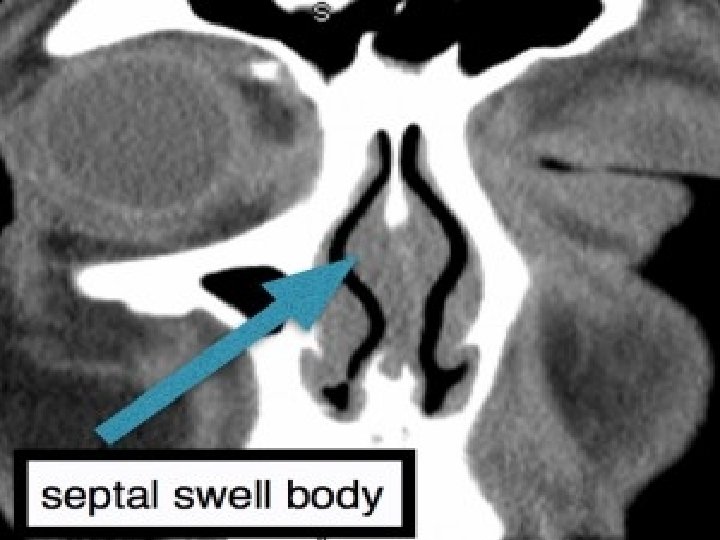

Nasal swell body(NSB) anatomical characteristics o Thickest and widest region of the nasal septum o Located at the level of the internal nasal valve o Anteriosuperior portion of the nasal septum o Overlying the cartilage and bone Nasal Septal Swell Body* (NSB) sagital CT image

Nasal swell body(NSB) = Septal turbinate

q. Can produce a significant effect on nasal resistance. Nasal Septal Swell Body* (NSB) coronal CT image q. Nasal obstruction Nasal Septal Swell Body* (NSB) axial CT image